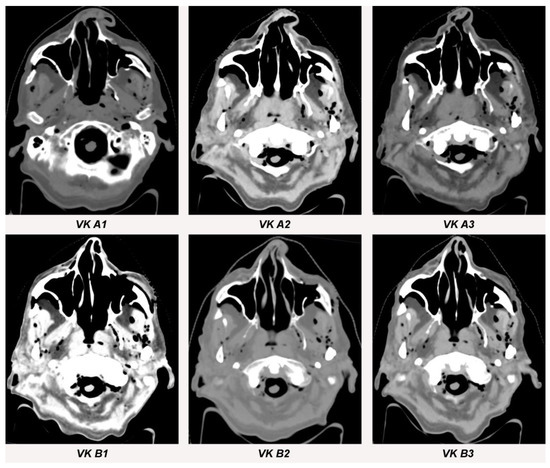

3.1. Streak Artifacts

3.1.1. Implant Material

3.1.2. Metallic Artifact Reduction Algorithm

3.2. Blooming Artifacts

3.2.1. Implant Material

3.2.2. Metallic Artifact Reduction Algorithm

3.3. Image Quality

| VESTAKEEP CF Filament-Fiber A1 | VK A1 | 63.3 (±5.9) | 11.0 (±2.4) | 0.213 |

| VESTAKEEP CF Filament-Fiber A2 | VK A2 | 80.3 (±5.0) | 28.0 (±6.1) | 0.085 |

| VESTAKEEP CF Filament-Fiber A3 | VK A3 | 68.0 (±7.5) | 15.7 (±3.3) | 0.151 |

| VESTAKEEP CF Filament-Fiber B1 | VK B1 | 64.7 (±6.7) | 12.3 (±3.9) | 0.164 |

| VESTAKEEP CF Filament-Fiber B2 | VK B2 | 62.3 (±7.6) | 10.0 (±2.8) | 0.243 |

| VESTAKEEP CF Filament-Fiber B3 | VK B3 | 66.0 (±9.5) | 13.7 (±3.1) | 0.155 |